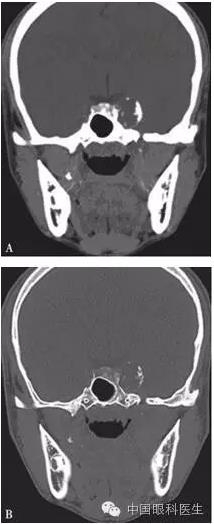

体格检查:双眼矫正视力0.8。右眼眼睑位置及眼球运动均正常,左眼上睑下垂,遮盖瞳孔上半部分,提上睑肌肌力4mm,左眼不能外展,上转、下转、内收运动均部分受限。患者右眼瞳孔直径3mm,左眼4mm;右眼对光反射灵敏,左眼迟钝,RAPD(-)。双眼眼底、眼压均正常。视觉诱发电位(visual evoked potential,VEP)、视野检查均未见明显异常。头颅MRI平扫+增强结果显示,左侧鞍旁海绵窦内T1WI稍低信号、T2WI稍高信号影,大小为21mm×23mm×22mm,增强扫描病灶呈不均匀强化,内可见多发的未强化区,左侧颈动脉海绵窦段受压外移,但结构未见明显损害(图2-3-0-1)。头颅CT平扫显示左侧鞍旁密度减低影,CT值为21Hu,大小为2.3cm,边缘可见钙化影,双侧眶内和球后未见异常(图2-3-0-2)。患者转入神经外科并行经额颞颧弓硬膜外入路左侧海绵窦区占位性病变切除术。术中快速冰冻切片病理学检查示,切除的组织标本富含黏液,制片困难。术后病理报告:左侧海绵窦区软骨源性肿瘤。考虑软骨瘤可能性大,局部细胞生长活跃,细胞间质伴黏液变性,免疫组织化学染色显示,肿瘤细胞对S-100和CK均呈阴性反应(图2-3-0-3)。术后患者左眼视力下降,额部及颊部皮肤感觉迟钝。眼科检查:右眼检查同术前,左眼矫正视力0.5,角膜上皮粗糙,角膜荧光素染色弥漫性着色,RAPD(-)。检眼镜检查示视盘界清,色红,视网膜血管走行正常,黄斑区未见明显异常。VEP、视野检查均未见明显异常。给予玻璃酸钠滴眼液点左眼、重组牛碱性成纤维细胞生长因子软膏涂左眼结膜囊并给予营养神经、改善全身血液循环药物治疗1周后,检查示见角膜上皮透明,角膜荧光素染色不明显,矫正视力0.8,左眼提上睑肌肌力测试可上提10mm。术后1个月复诊见,上睑下垂治愈,眼球运动受限明显好转。

注:A.软组织窗;B.骨窗。左侧鞍旁可见密度减低影,CT值21Hu,大小约为2.3cm,边缘可见钙化影,双侧眶内和球后未见异常